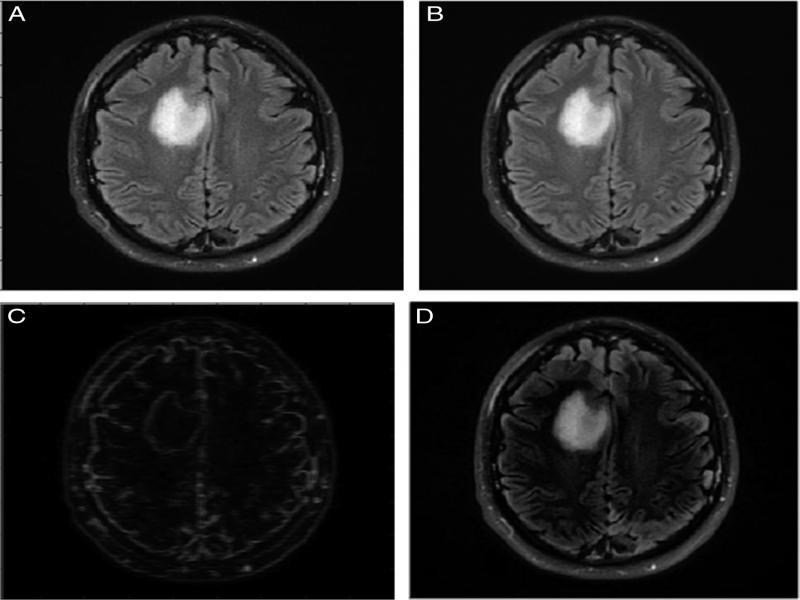

Top-hat filter: The top hat filter removes noise from the foreground of the image. It does so by extracting small elements and details from the image (Figure 3).

Contrast enhancement: Contrast is enhanced by saturating the top 1% and bottom 1% of the intensity values (Sara et al., 2019).

Image binarization: This is carried out to convert the entire image into a matrix of 1s and 0s depending on the intensity value. The output thus obtained is a black and white image.

Morphological operations: Morphological erosion removes any excess pixels from the boundaries of various regions while morphological dilation adds pixels to fill in any gaps and holes within the boundaries (Figure 4).

Figure 3:

Pre-processing phase 1. (A) Grayscale image, (B) Image after median filter, (C) Image after smoothening, (D) Image after top-hat filter.

Figure 4:

Pre-processing phase 2. (A) Contrast enhancement, (B) Image after binarization, (C) Image after morphological erosion.